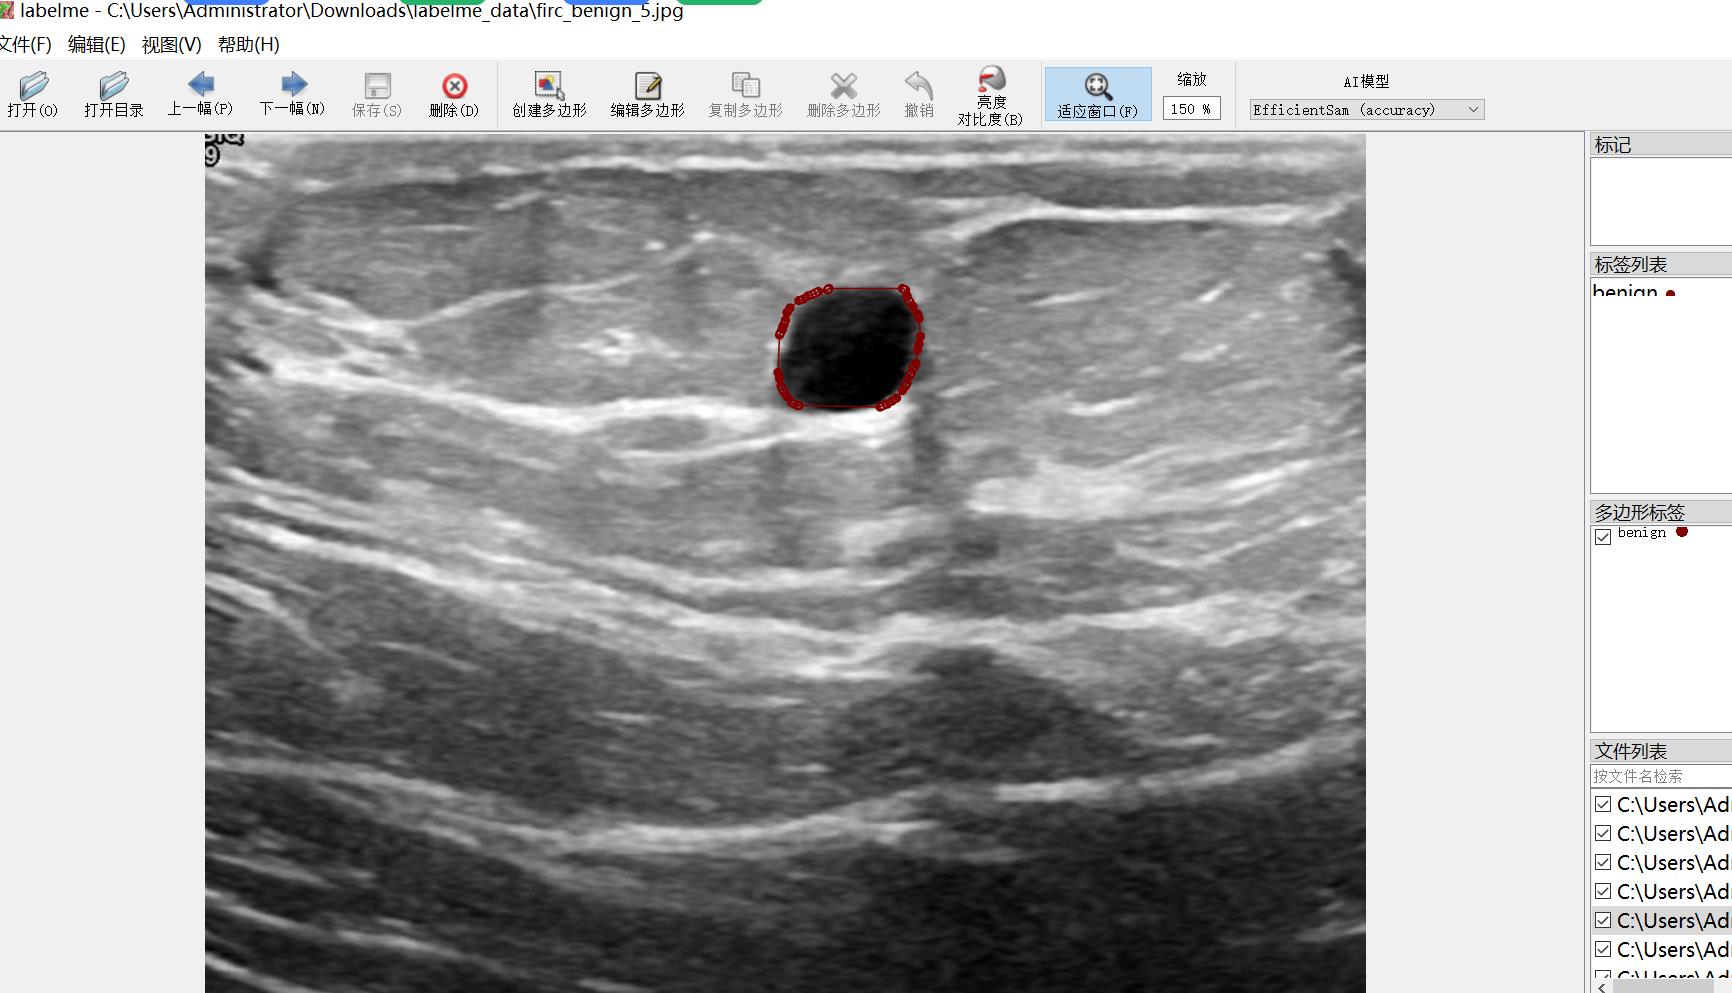

标注类别名称:["benign","malignant"]

benign count = 467

malignant count = 248

标注规则:对类别进行画多边形框polygon

标注例子: